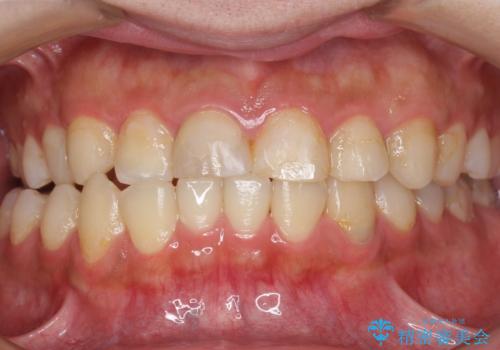

咬み合わせが悪く矯正も検討されていたそうですが、歯を真っ白にしたいというご希望もあり、28本のすべての歯をセラミックにしたいとのことでした。

精査したところ、ほとんどの歯が保険内のレジンで充填されており、咬み合わせも悪く咬合していない歯もありました。

虫歯をしっかりと治療したのち、オールセラミッククラウンによる補綴治療を行いました。